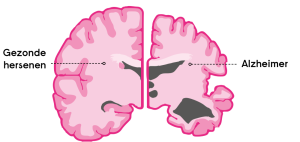

چرت روزانه در سالمندان ممکن است نشانه زوال عقل / بیماری آلزایمر باشد

چرت زدن در طول روز در سالمندان بخش طبیعی از دوره پیری است، اما ممکن است بیماری آلزایمر و سایر زوال عقل را نیز پیشبینی کند. بر اساس مطالعه ای جدید، زمانی که زوال عقل یا علائم معمول آن، اختلال شناختی خفیف، تشخیص داده شود، دفعات و یا مدت چرت زدن به سرعت افزایش مییابد.

این مطالعه که توسط دانشگاه California ، San Francisco (UCSF) و دانشکده پزشکی Harvard به همراه Brigham و بیمارستان زنان، زیرمجموعه آموزشی آن انجام شد، از این نظریه که چرت روزانه در افراد مسن صرفاً برای جبران کم خوابی شبانه عمل میکند، فاصله میگیرد. در عوض، محققان در مقاله خود که اخیراً در مجله آلزایمر و زوال عقل منتشر شده که به کار سایر محققان UCSF اشاره میکند، نشان دهنده این است که زوال عقل ممکن است بر نورونهای محرک بیداری در نواحی کلیدی مغز تأثیر بگذارد.

از دست دادن نورونهای بیدارکننده ممکن است باعث چرتهای طولانیتر شود

به گفته محققان، افزایش چرت زدن ممکن است با مطالعه دیگری راجع به مقایسه مغز پس از مرگ افراد مبتلا به بیماری آلزایمر با افراد بدون اختلال شناختی توضیح داده شود که سال 2019 توسط سایر محققان UCSF انجام شد. افراد مبتلا به بیماری آلزایمر نورونهای تحریک کننده بیداری کمتری در سه ناحیه مغز دارند. به نظر میرسد این تغییرات عصبی با درهم تنیدگیهای تائو (ریسمان) مرتبط باشد که یکی از مشخصه های بارز آلزایمر است و با افزایش فعالیت آنزیمهایی مشخص میشود که باعث در هم تنیدن و چین خوردگی نادرست پروتئین میشود.